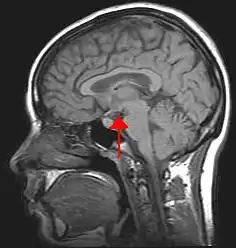

Hipotalamusul (din greaca veche ὑπό, „sub”, și θάλαμος, „cameră”) este o porțiune a creierului care conține un număr de nuclei mici cu o varietate de funcții. Una dintre cele mai importante funcții ale hipotalamusului este legarea sistemului nervos de sistemul endocrin prin intermediul glandei pituitare.Hipotalamusul este situat sub talamus și face parte din sistemul limbic. [1] În terminologia neuroanatomică, formează partea ventrală a diencefalului. Toate creierele vertebratelor conțin un hipotalamus. La om, este de mărimea unei migdale.

![]() Localizarea hipotalamusului uman | |

![]() Localizarea hipotalamusului în raport cu glanda hipofiză și restul creierului (colorat în albastru) | |